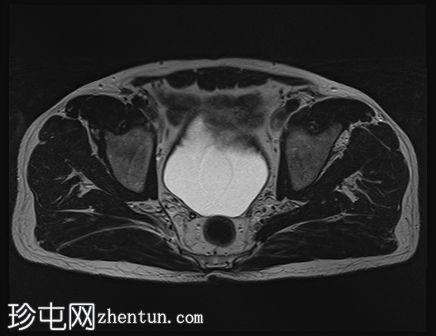

轴位

T2加权像

左侧股直肌近端至中段肌纤维内可见一长条状、边界清晰的肌内肿块,其大小约为:头尾径14.4 cm,横径6.6 cm,前后径2.7 cm。

该病灶在所有序列上均呈脂肪信号,T1加权像上呈高信号,脂肪抑制像上信号完全抑制(假性高信号)。

未见厚间隔、结节状结构或非脂肪成分。

MRI 显示左侧股直肌内存在脂肪瘤。

虽然 MRI 特征未提示恶性肿瘤,但体积较大、位置较深或位于下肢的病变会增加恶性肿瘤的可能性,在这种情况下,建议进行活检并开展分子检测。